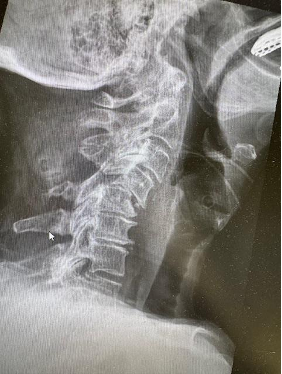

If needed, diagnostic imaging may include:

• X-rays to evaluate spinal alignment

• MRI scans to assess discs, nerves, and soft tissues

• CT scans to examine bone structures